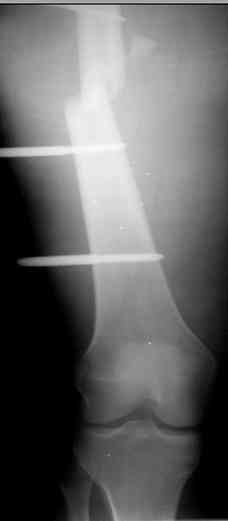

И тракцию бедра на стержне. Типа (СМ картинки).

После выращивания регенерата стержень блокировать.

Если у Вас возникнут какие-то сомнения, то возможно наложение гибридного циркулярного-монолатерального дистракционного аппарата на левое бедро и выполнение остеотомии в в/3 бедра. Почему монолатеральный гибридный аппарат, а не аппарат Илизарова? Эта конструкция гораздо легче переносится пациентами, в ней гораздо удобнее проводить местное лечение ран.

Разрешите рассказать о пациенте, которому мы фиксировали перелом такой конструкцией.

Больной 19 ти лет, пострадал в результате ДТП, пассажир мотоцикла. Получил открытый оскольчатый перелом н/3 левой бедренной кости 3a тип по Гастилло-Андерсену. При поступлении ПХО ран, фиксация стержневым аппаратом наружной фиксации. Лечение больного осложнилось развитием анаэробной флегмоны левого бедра. Лампасные разрезы, неоднократные некрэктомии, некротизировался участок диафиза левой бедренной кости на протяжении 15 см. Произведена резекция. 20.05.10- демонтаж АНФ, остеоситез левой бедренной кости гибридным циркулярно-монолатеральным стержневым дистракционным аппаратом наружной фиксации, остетомия левой бедренной кости в в/3. Сейчас начата дистракция в аппарате, проводится подготовка ран к аутодермопастике.